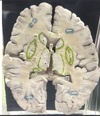

1. Identify the structure labelled 1. 2. Identify the structure labelled 2. 3. Identify the structure labelled 3 4. Identify the structure labelled 4. 5. Identify the specific structure labelled 6.

1. Head of Caudate 2. Globus pallidus of lentiform nucleus 3. Putamen of lentiform Nucleus 4. Thalamus 5. Genu of corpus callosum

1. Identify the specific structure labelled 7. 2. Identify the specific structure labelled 8. 3. Identify the specific structure labelled 9. 4. Identify the specific structure labelled 11. 5. Identify the structure labelled 14.

1. Anterior Limb of internal Capsule, frontopontine, thalamocortical 2. Genu of Internal Capsule 3. Posterior limb of Internal capsule, corticospinal 4. Spleenium of corpus callosum 5. Insular cortex

1. Identify the structure labelled 5. 2. What is the immediate medial relation of the identified structure? 3. What is the immediate lateral relation of the identified structure?

1. Claustrum thin, irregular, sheet-like neuronal structure hidden beneath the inner surface of the neocortex in the general region of the insula. Its function is enigmatis 2. Putamen 3. Insular Cortex

1. Identify the structure labelled 10. 2. Where does this structure commence? 3. Where does this structure end? 4. From the cavity of lateral ventricle, what layers must be traversed in order to access the structure labelled 10?

1. Optic Radiation 2. Lateral Geniculate body 3. Primary visual cortex (calcarine fissure) 4. Ependymal layer, Tapetal layer

1. Identify the specific space labelled 12. 2. What is the embryonic origin of this structure? 3. Identify the specific space labelled 13. 4. What is the embryonic origin of this structure?

1. Anterior horn of lateral ventricle 2. Cavity of telencephalic vesicle 3. Posterior horn of lateral ventricle 4. Neural tube